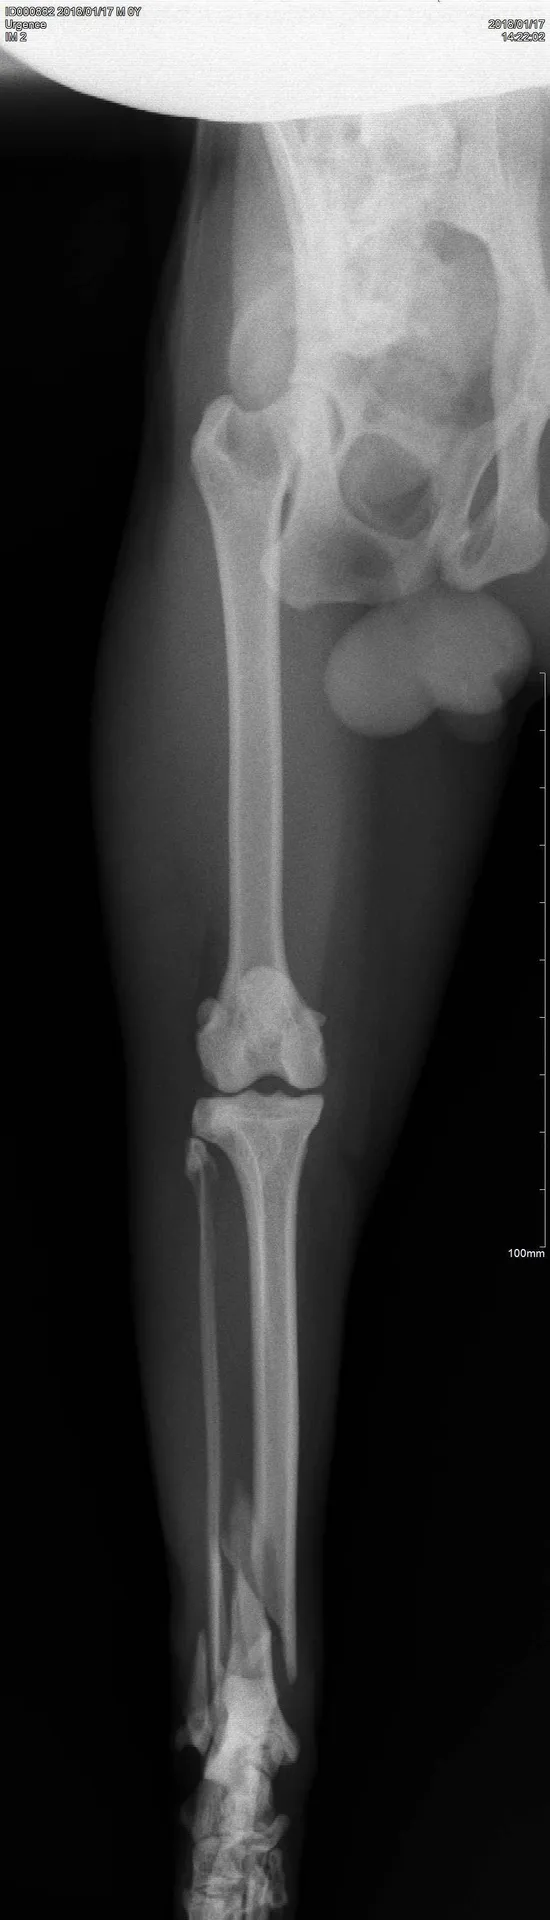

radiographie chat à Toulon

FAIRE UNE RADIOGRAPHIE POUR CHIEN CHAT NAC SUR TOULON

Qu’est-ce qu’une radiographie ?   Une radiographie est un examen d’imagerie consistant à la prise de cliché au moyen d’un appareil à rayon X ceci afin de visualiser les différentes structures internes. Quand effectuer une radiographie ? La radi...